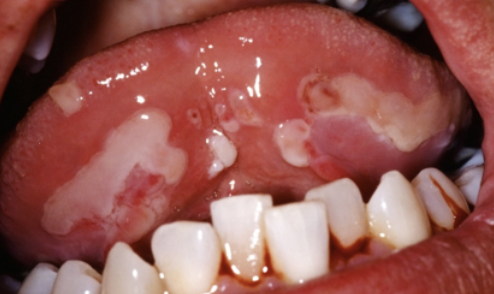

Wat zijn aften?

Ziet er zweerachtig en wit uit met rood eromheen. De oorzaak hiervan is nog onbekend. Wel weten we dat het een reactie is op een bepaalde stof. Bevorderende factoren zijn traumatische beschadiging van de slijmvliezen, overgevoeligheid vanvoedingsstoMen, hormonale schommeling en stress. Een normale aft is niet groter dan 0,5 cm en verdwijnt na 7-10 dagen. Een grote aft is groter dan 1 cm en verdwijnt pas na 4-6 weken. Deze laat meestal een litteken achter.